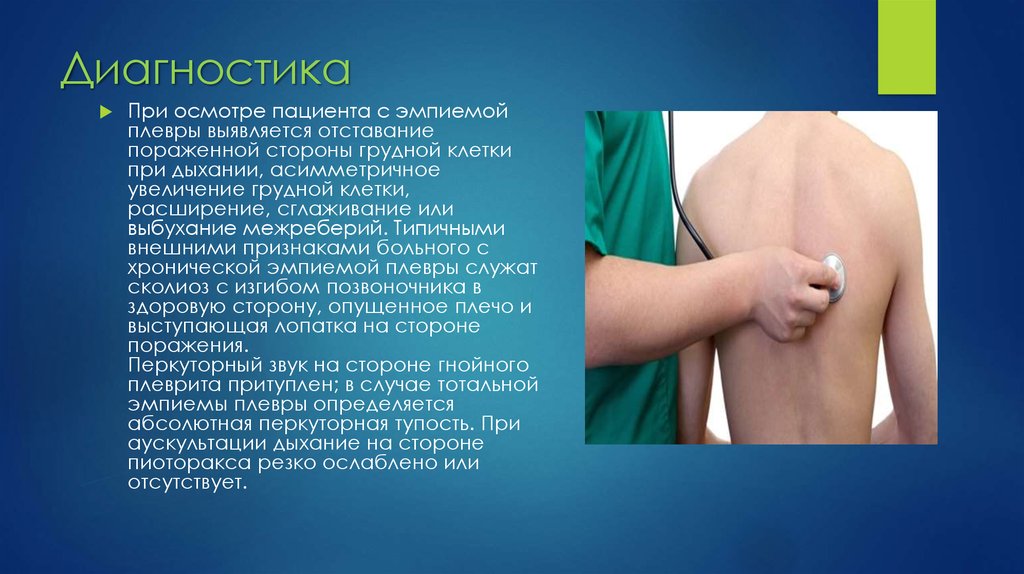

Дифференциальная диагностика заболеваний плевры